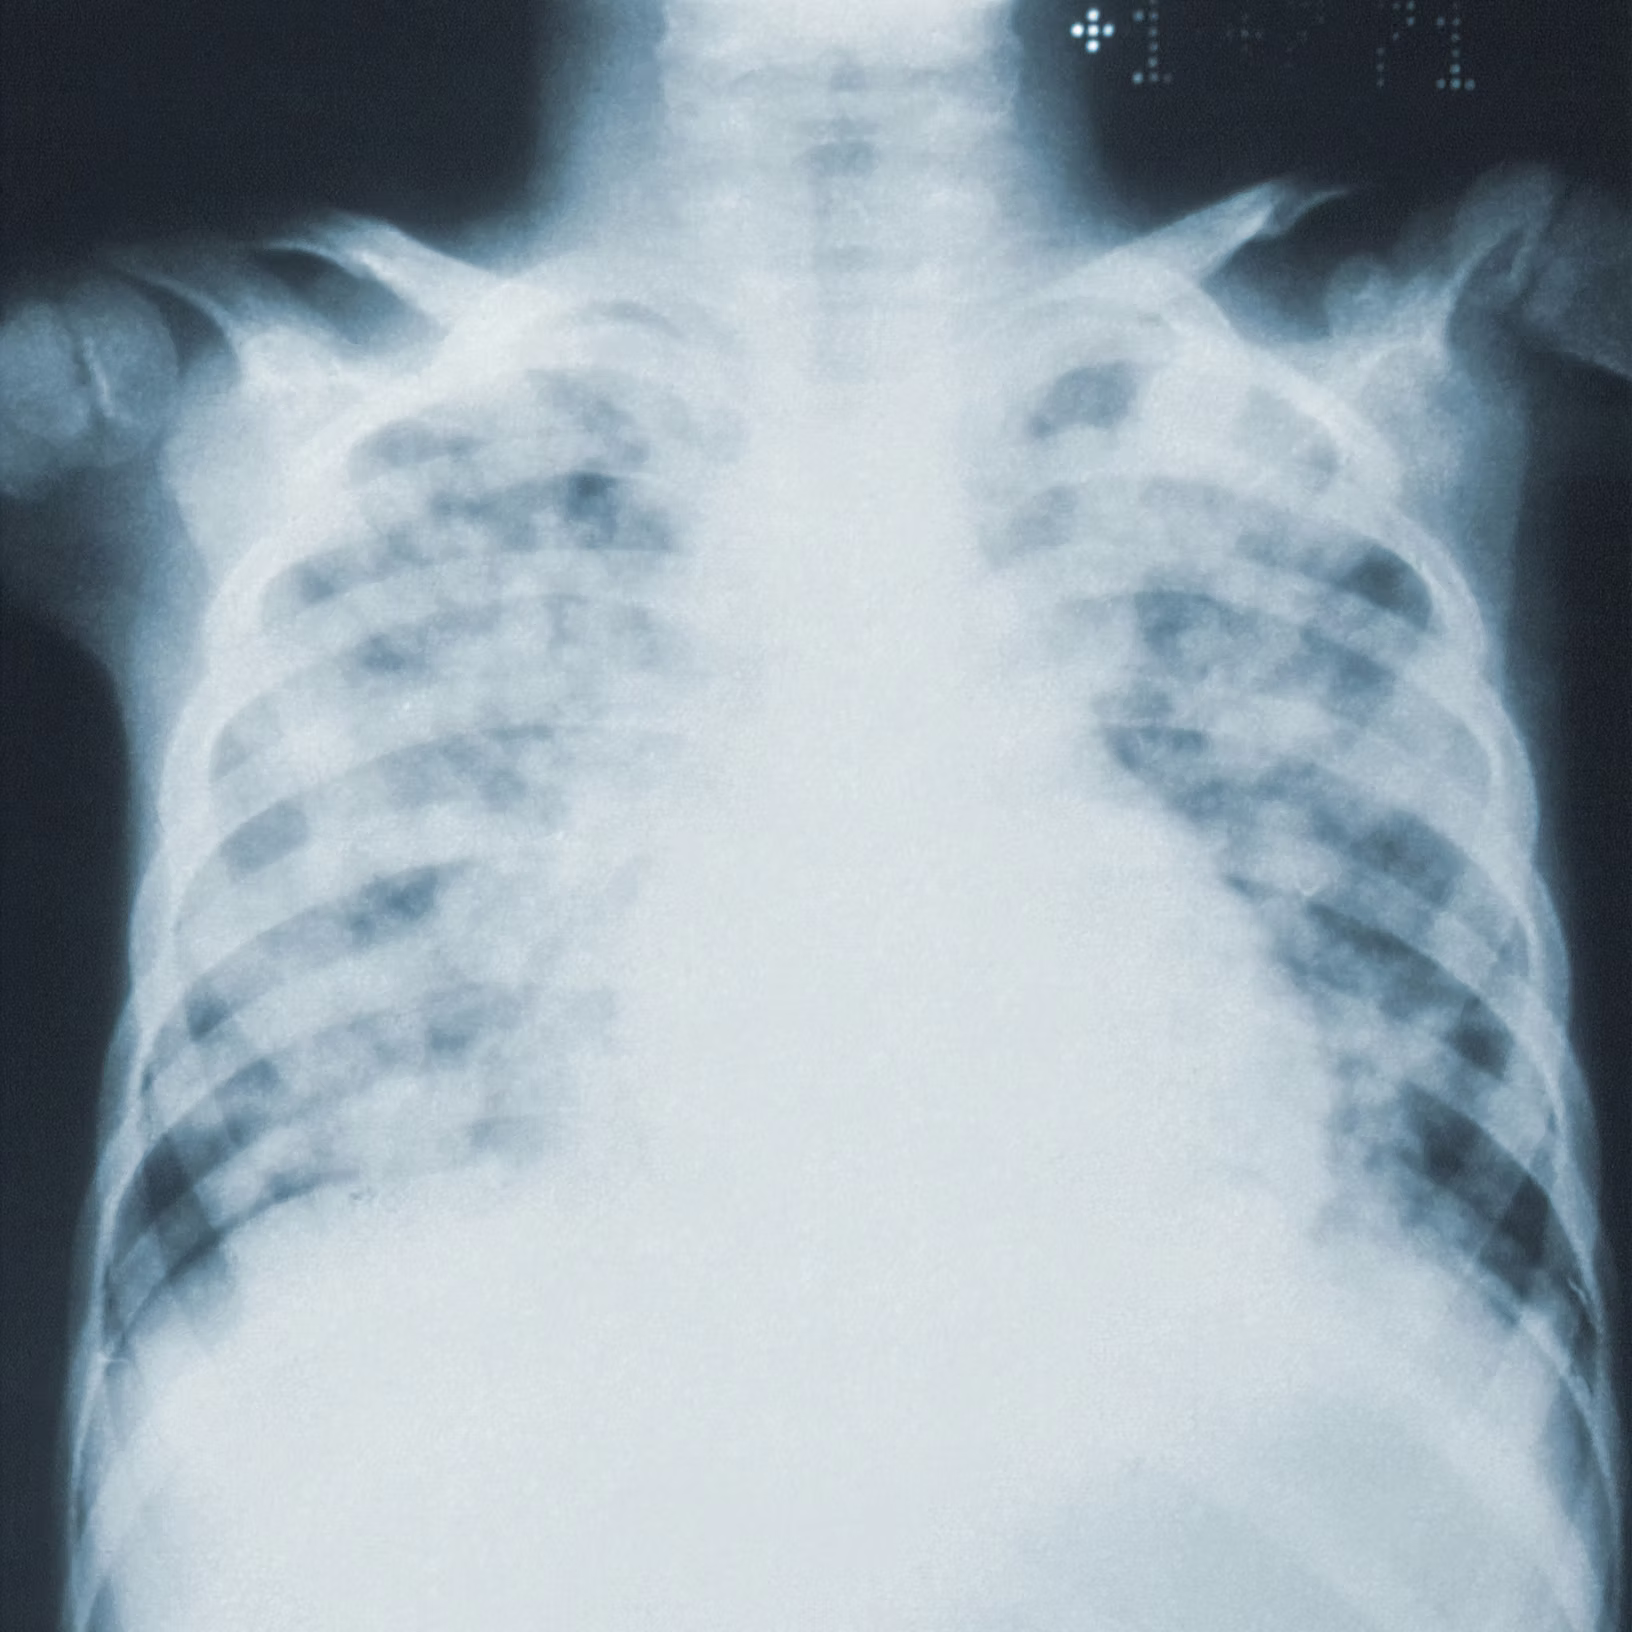

Modified Nuss procedure for the treatment of pectus excavatum.

The Wung procedure is a modified surgical technique based on the classic Nuss procedure, which has been meticulously adapted to overcome its inherent limitations and risks. Although it utilizes the lever principle of the Nuss procedure, the Wung procedure introduces significant differences in operative details.

Indications

Chest Wall Deformity

Non-Chest Wall Deformity